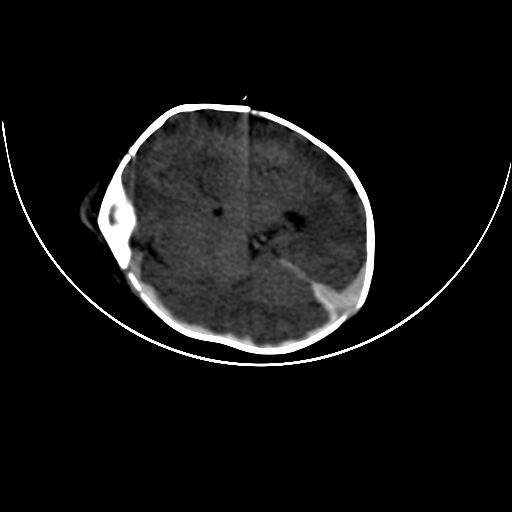

标题: PED0836: 新生儿

双侧硬膜下血肿并蛛网膜下腔出血。

双侧硬膜下血肿并蛛网膜下腔出血

硬膜下及蛛网膜下腔出血。

hie 蛛网膜下腔出血,硬膜下血肿。

hie;双侧硬膜下血肿并蛛网膜下腔出血

hie,双侧硬膜下血肿并蛛网膜下腔出血

双侧硬膜下血肿并蛛网膜下腔出血,考虑维生素k缺乏引起.

较大范围出血,应考虑维生素k缺乏引起,结合临床吧。

好像脑实质没有明显低密度影,各位大侠怎么支持hie呢?